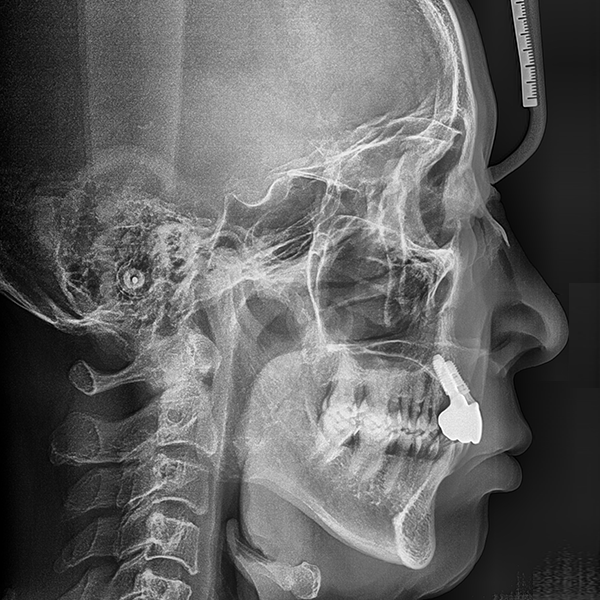

3. 症例.153 60代 イ*ゲ 2020-01-19 / 2020-1-20

上顎/前歯部 / 4本以上 / 骨移植|高血圧

症例.153 60代 イ*ゲ 2020-01-19 / 2020-1-20